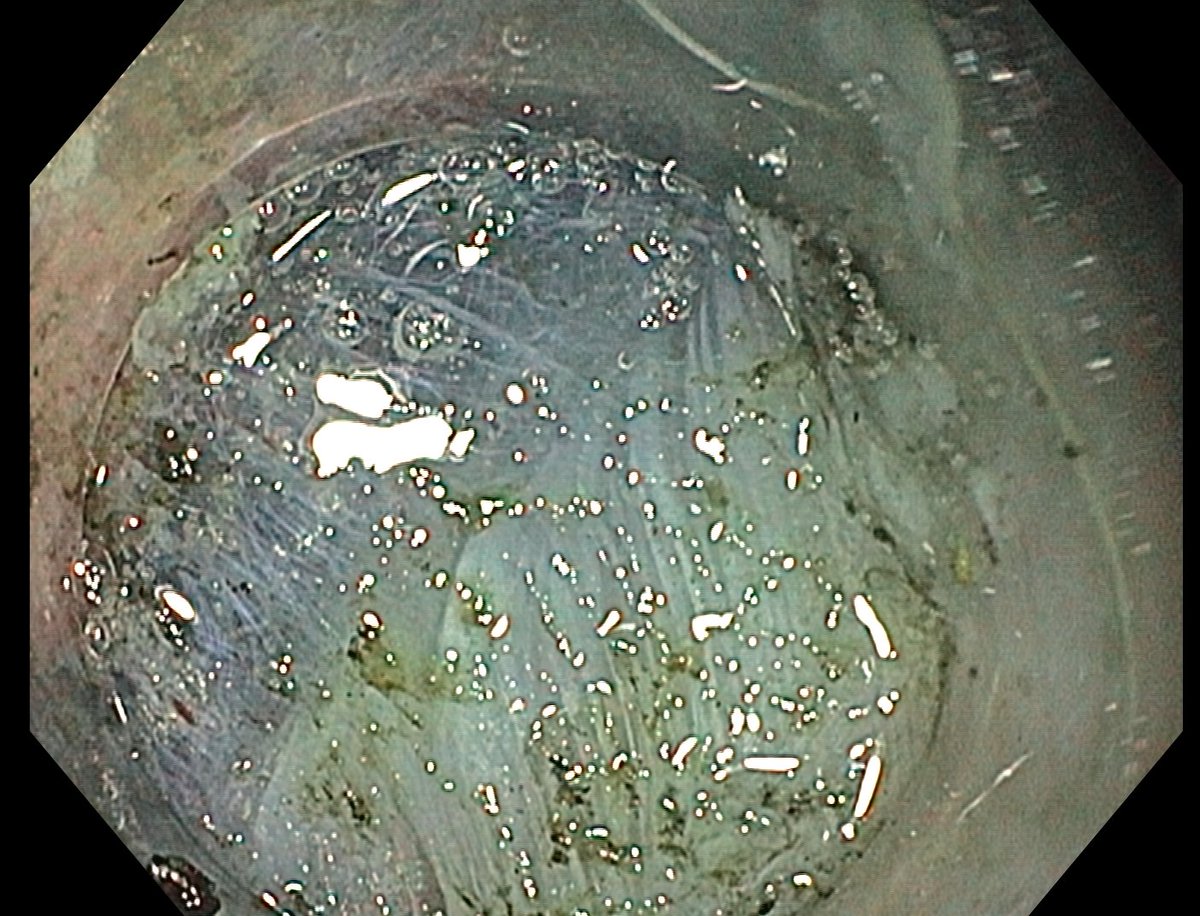

📢 March 2026 Issue #ACGCRJ 📷: Endoloop assisted hot snare polypectomy of a large brunner gland hamartoma in distal duodenum using colonoscope.🔦 🔗journals.lww.com/acgcr/pages/cu… @DushDahiya @DaniyalAbbasMD @AmCollegeGastro